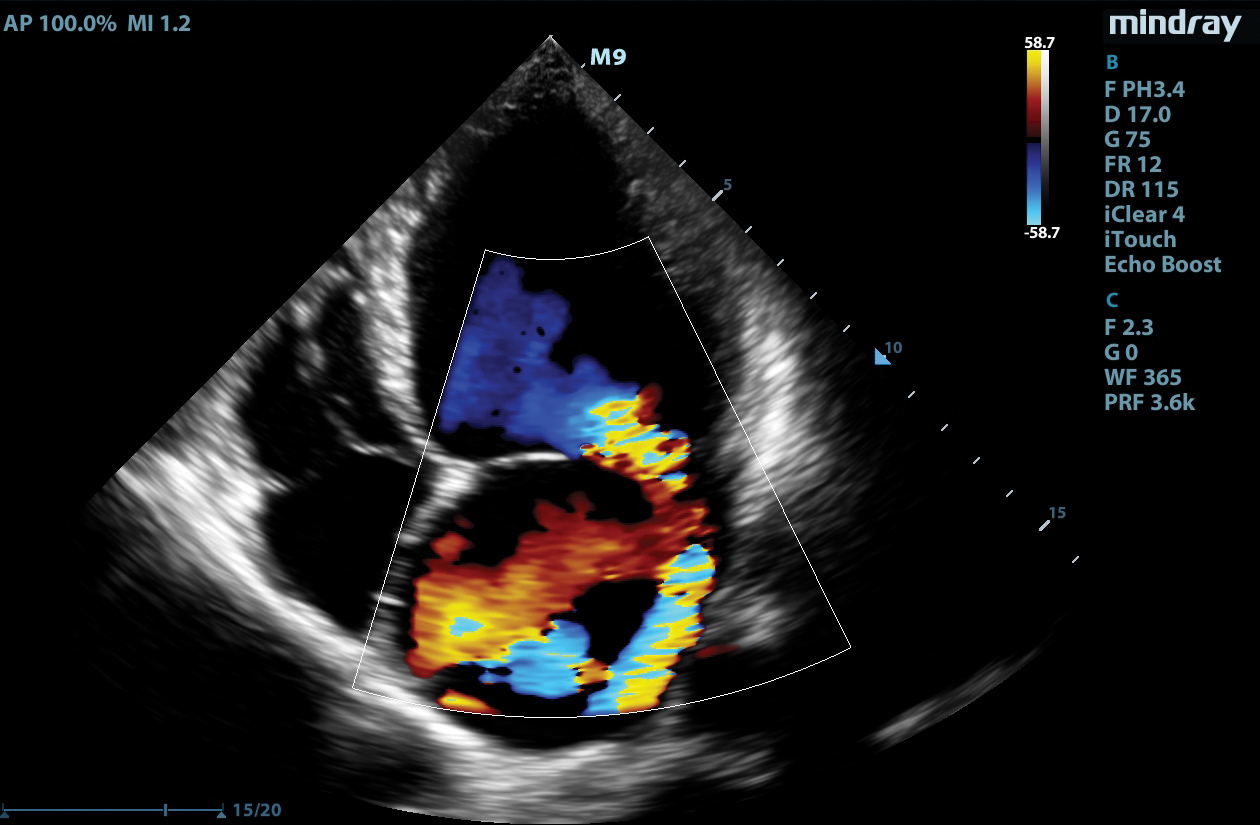

LVO with Stress Echocardiography

The combination of LVO during stress examinations enhances differentiation between tissue and the blood pool, providing better visualization of the endocardium. This package includes customizable user protocols, flexible wall motion scoring, and a comprehensive reporting suite.

Tissue Tracking

Mindray’s Tissue Tracking technology with quantitative analysis allows users to monitor the displacement of cardiac tissue by tracking the speckle displacement in the image from frame to frame. This non-angle dependent tool with onboard analysis, can be performed at the bedside, saving time and simplifying challenging cases.